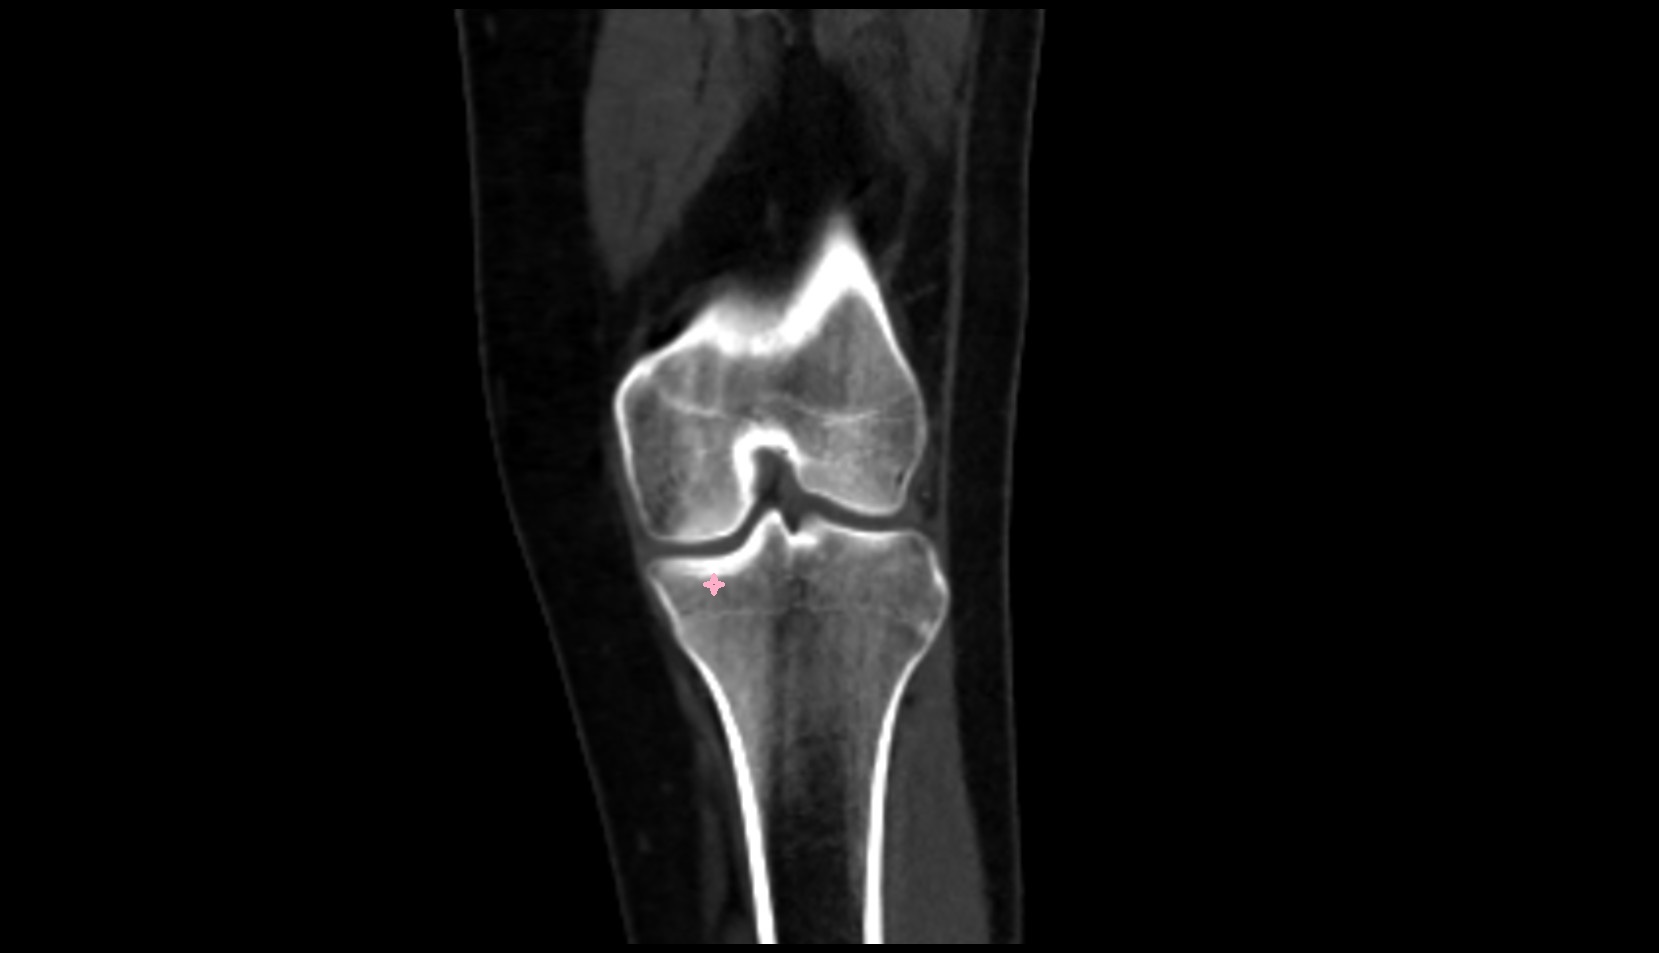

- Knee Joint